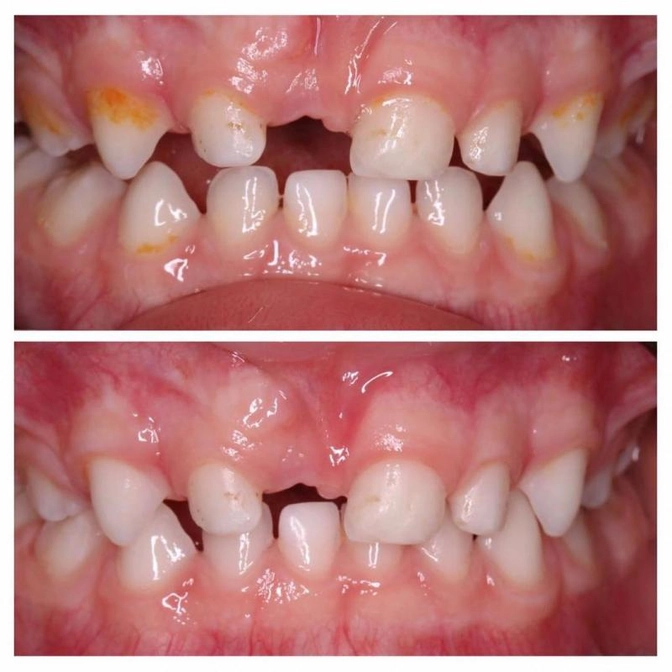

Клинический случай: преждевременная потеря центрального молочного зуба

Маленькому пациенту всего три года, и это не естественная смена молочного зуба.

Желтое - это налет на всех зубах. Ребенок не дружит с зубной щеткой, а родители и не настаивали.

Провели профессиональную чистку и, конечно, обнаружили кариес.

Но что же все-таки случилось с центральным резцом?

1,5 года назад малыш упал и выбил этот зуб.

Это называется полный вывих зуба.

И из-за его преждевременной утраты соседние стали смещаться на пустующее место.

А ведь у малыша короткая уздечка верхней губы.

И ещё, у ребёнка есть тенденция к формированию глубокого прикуса.

Видите, верхние зубки сильно перекрывают нижние.